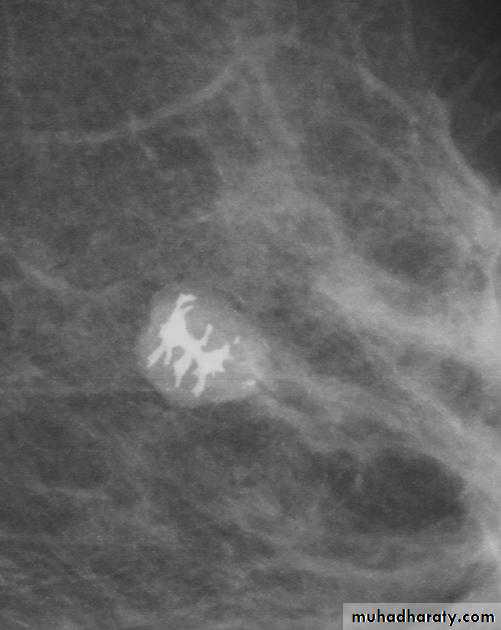

Ca breast

A…..Invasive ductal carcinoma is a subset of ductal carcinoma. It is an infiltrating, malignant and abnormal proliferation of neoplastic cells in the breast tissues. It is the most frequently seen breast malignancy .Radiographic features

Mammogramspiculated hyperdense lesion

oval/lobulated lesion

microcalicifications

Micro calcifications

Micro calcifications are tiny specks of calcium in the breast. Micro calcifications seen on a mammogram are of more concern than macrocalcifications, but they do not always mean that cancer is present. The shape and layout of microcalcifications help the radiologist judge how likely it is that cancer is present.

In most cases, the presence of microcalcifications does not mean a biopsy is needed. But if the microcalcifications have a suspicious look and pattern, a biopsy will be recommended. (During a biopsy, the doctor removes a small piece of the suspicious area to be looked at under a microscope. A biopsy is the only way to tell if cancer is really present.)